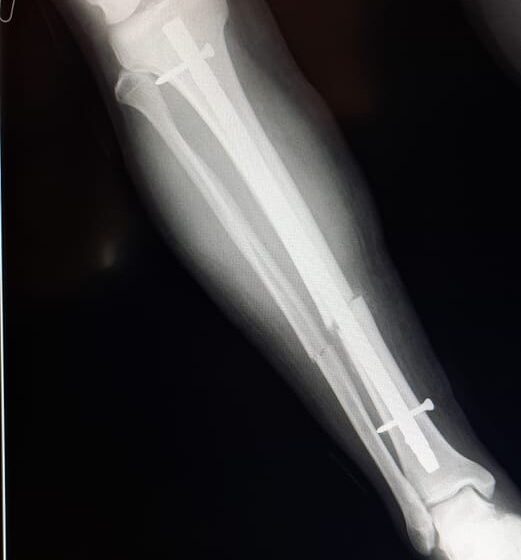

Se realizó una osteosíntesis endomedular de pierna derecha a un hombre de 35 años que no posee obra social. La prótesis fue solventada en su totalidad por el sistema público de salud. La cartera sanitaria destacó la realización de este tipo de cirugía en un hospital subzonal.

El Gobierno del Chubut, a través de la Secretaría de Salud provincial, destacó la reciente realización de una importante intervención quirúrgica, con colocación de una prótesis, en el Hospital Subzonal de El Maitén a un hombre de 35 años, sin obra social.

La operación se concretó este miércoles 3 de enero y fue encabezada por profesionales de dicho nosocomio y del Hospital Zonal de Esquel, y el costo de la prótesis, que ascendió a 1.200.000 pesos, fue solventado en su totalidad por el sistema público de salud desde el Área Programática Esquel.

El procedimiento se llevó adelante teniendo en cuenta que el hombre se había fracturado la tibia y el peroné derecho.

El equipo quirúrgico que efectuó la osteosíntesis endomedular de pierna derecha, estuvo conformado por los médicos traumatólogos Enzo Fuentes, del Hospital Subzonal de El Maitén, y Javier Galván y Juan Ayestaran, del Hospital Zonal de Esquel; y el médico anestesiólogo Luis Miy, del Hospital de El Maitén.